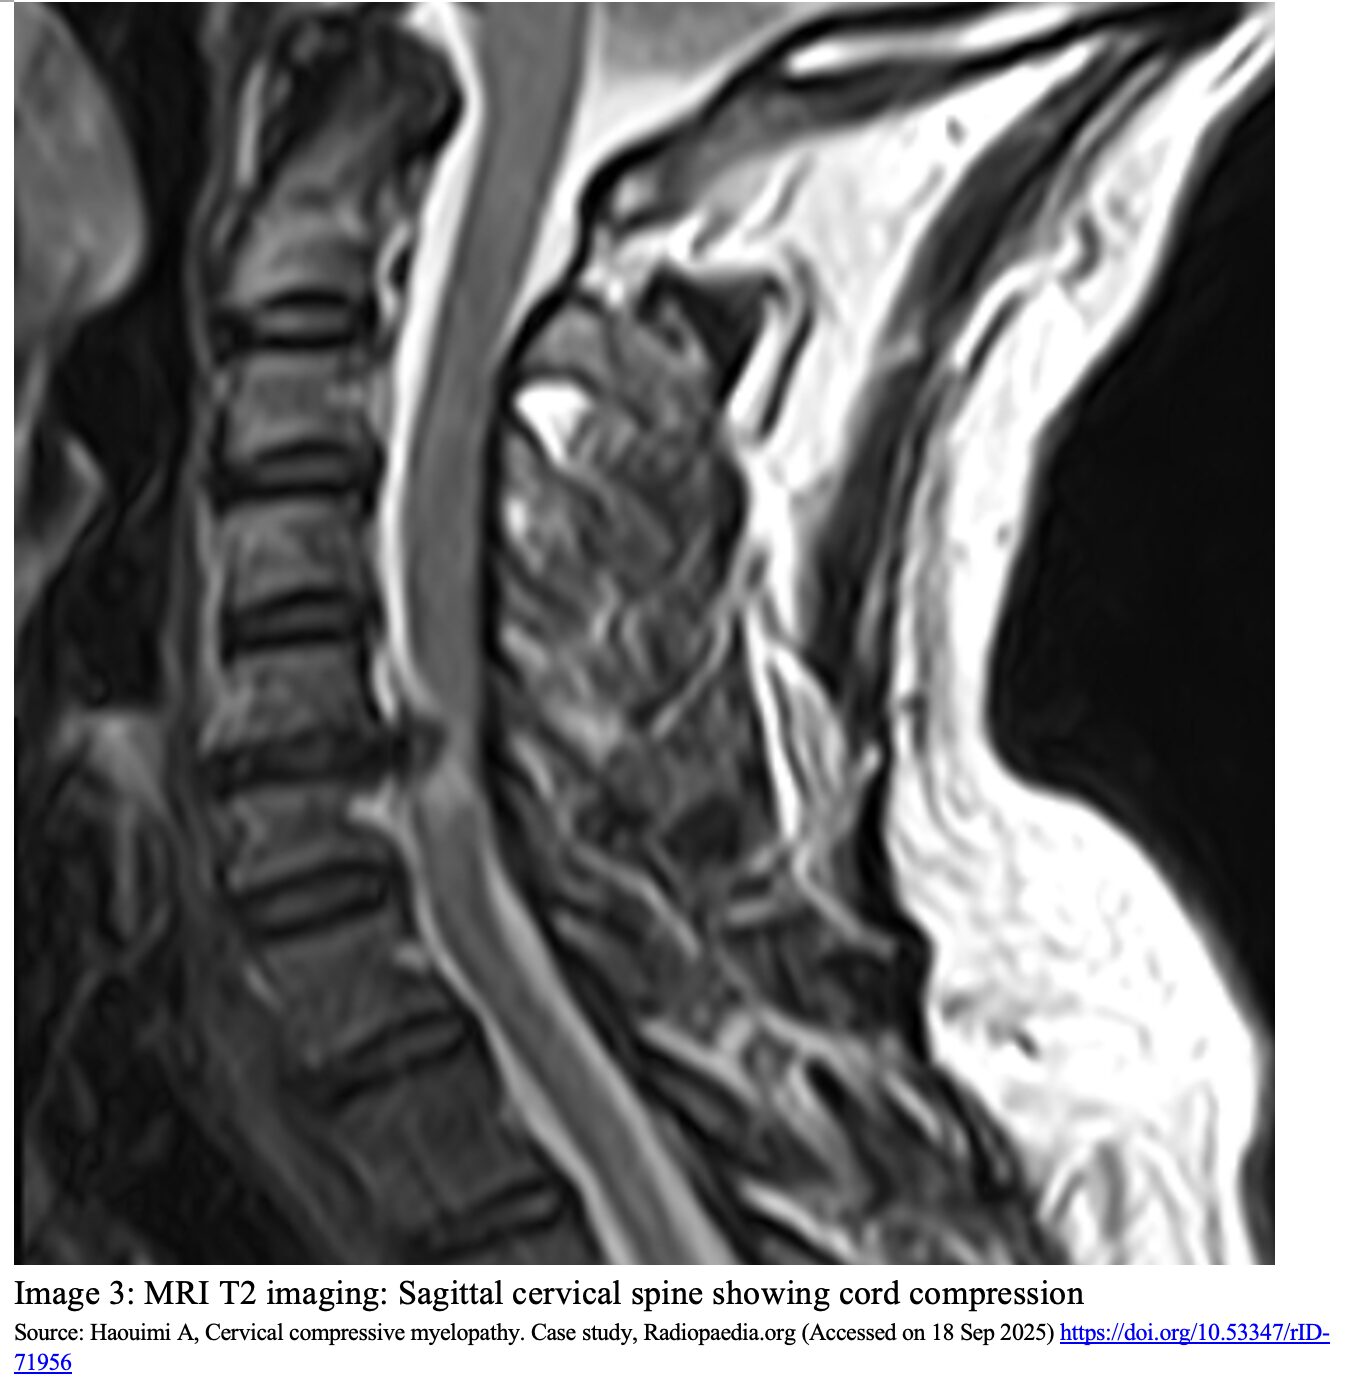

- MRI with and without contrast is the gold standard for assessing compression of the spinal cord (image 3).1,10

- MRI with neck in a neutral position has a sensitivity of 81.4% and specificity 88.3%. Increased sensitivity and specificity when MRI done with neck in extension.14,15

- Lack of full circumferential hyper-intensity on T2-weighted surrounding the cord can suggest some degree of stenosis from disruption of spinal fluid.10

- Deformity of the spinal cord can appear as a “kidney bean” with flattening of one side.

- Hypo-intense signaling within the cord on T1-weighted imaging suggests a greater degree of cord injury, advanced disease, and a poorer prognosis.1